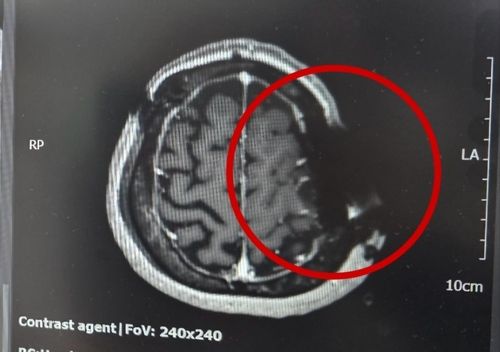

머리뼈에 박힌 톱날 머리뼈에 박힌 톱날

동그라미 속 화살표가 가리키는 물체가 머리뼈에 박혀있는 쇠톱 날이라고 한다. 뇌종양 환자 A씨가 유명 대학병원에서 뇌수술을 받다 머리뼈에 톱날이 박혔는데 모르고 그냥 봉합했다가 재수술을 받았다. [B씨 제공]